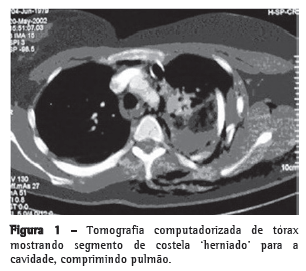

Paciente do sexo feminino, 32 anos, vítima de acidente automobilístico, que ocasionou hemopneumotórax esquerdo, contusão pulmonar esquerda e fraturas duplas do terceiro ao oitavo arcos costais esquerdos, evidenciados na radiografia e tomografias computadorizadas (TC) do tórax (Figuras 1 e 2). As tomografias de crânio, coluna cervical, abdômen e pelve apresentaram-se normais, assim como eletrocardiograma, ecocardiograma, enzimas musculares e marcadores de necrose miocárdica. Foi realizada drenagem torácica fechada em selo d'água e solicitada a instalação de cateter epidural para analgesia contínua com bomba de infusão. A paciente apresentava deformidade torácica importante e dor, apesar de doses elevadas de analgésicos. Antecipou-se que o quadro, se não tratado cirurgicamente, evoluiria para deformidade complexa da parede, com possível acometimento da respiração. Não necessitou de ventilação mecânica. Em vista desse quadro clínico, foi decidido o tratamento cirúrgico para estabilização das fraturas. O procedimento foi realizado por toracotomia póstero-lateral esquerda. Foram encontradas fraturas duplas do terceiro ao oitavo arcos costais esquerdos com ruptura completa de vários pedículos intercostais, herniação e impactação do segmento fraturado (6 arcos) para o interior da cavidade pleural, com compressão importante do parênquima pulmonar (toracoplastia traumática). Foi realizada redução das fraturas e fixação das costelas com fios de aço número 5, perfurando as extremidades das costelas com broca número 2, passando-se o fio de um segmento de costela para outro e amarrando-se o fio de aço. Foi colocado um dreno de tórax, que foi retirado no terceiro dia. A paciente evoluiu com excelente controle da dor e melhora na dinâmica ventilatória. A radiografia e a tomografia no pós-operatório confirmam o bom resultado do tratamento cirúrgico. (Figura 3).

O trauma fechado de tórax é uma importante causa de morbidade e mortalidade, principalmente quando há tórax instável. É observado quando ocorrem múltiplas fraturas da caixa torácica, mais especificamente quando observamos fraturas de três ou mais costelas, em 2 ou mais pontos, havendo flutuação, movimento respiratório paradoxal, ou ambos.(3) A toracoplastia traumática pode ser definida como a condição na qual o segmento fraturado migra para dentro do tórax e é envolvido pelos segmentos dos arcos costais fixos, causando impactação desse segmento no interior da cavidade pleural. Isto causa dor intratável (tração permanente de nervos intercostais) e comprime o parênquima pulmonar, piorando consideravelmente o quadro clínico do paciente. O tórax instável grave está associado à falência respiratória, por retenção de secreções, atelectasia, pneumonia e restrição da movimentação da caixa torácica mais tardiamente.(2) A instabilidade torácica pode ser tratada eficientemente com analgesia, preferencialmente epidural, e fisioterapia, com mobilização adequada de secreção.